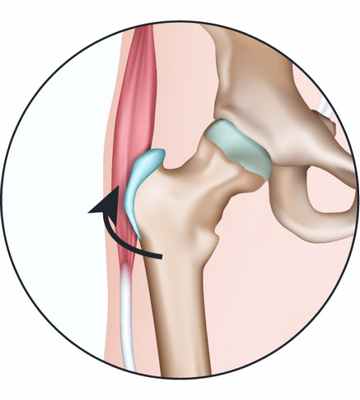

При сгибании ноги в тазобедренном суставе сухожилия сдвигаются и оказываются кпереди от большого вертела. Так как большой вертел слегка выступает, то при движении сухожилий относительно него можно услышать щелчок. Такое состояние может привести к бурситу тазобедренного сустава. Бурсит - это воспаление и утолщение синовиальной сумки: мешка с гладкими стенками, заполненного жидкостью, который обеспечивает беспрепятственное скольжение мышц относительно костей.

Синдром щелкающего бедра может быть вызван сухожилием прямой мышцы бедра, которая проходит по передней поверхности бедра и крепится к тазовой кости. При сгибании бедра сухожилие смещается относительно головки бедренной кости; при выпрямлении нижней конечности сухожилие возвращается в исходное положение. Эти возвратно-поступательные движения сухожилия по поверхности головки бедренной кости и вызывают щелчки.